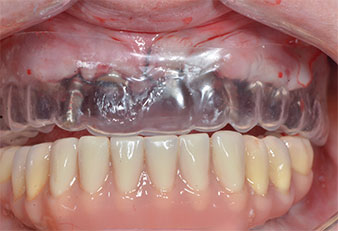

A causa dell'osso relativamente duro (D2) in quest'area, le sedi dell'impianto di 10 mm nelle posizioni 11 e 21 sono state finalizzate con un trapano rotante da 4 mm di diametro, in combinazione con un contrangolo chirurgico W&H WS-75 L, il motore per impianto W&H Implantmed e il modulo opzionale Osstell ISQ di W&H. Al contrario, a causa dell'osso morbido, le sedi posteriori sono state preparate a un diametro finale di 3 mm utilizzando lo strumento Piezomed I3P. Gli impianti sono stati infine posti per via transgengivale sull'osteointegrato per tre mesi (Figg. 6-10). La protesi dentaria esistente è stata mantenuta su quattro impianti provvisori (Fig. 8).